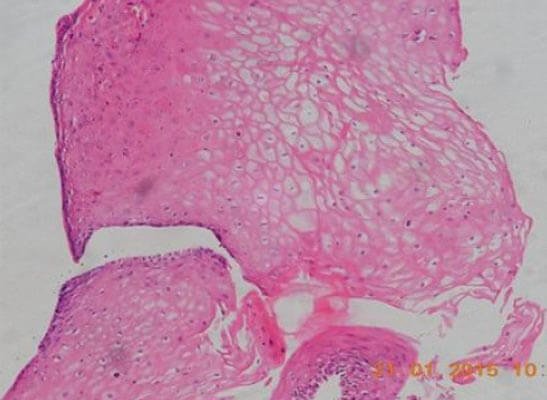

Figure 3: Photomicrograph of tissue from the implanted site of the urethra showing stratified squamous epithelium

After urethral catheter removal, all patients voided well with a good stream. There was a symptomatic improvement in all patients, and uroflow improved with a mean flow of 24 mL/s. The check Urethroscopy carried out at 6 months, 1 year and after 2 years are shown in Fig 2,3,4. Four patients were voiding well and did not require any auxiliary procedure at 3 years of follow up. Recurrence was seen in two patients at 18 months in one patient and at 2 years in the other.